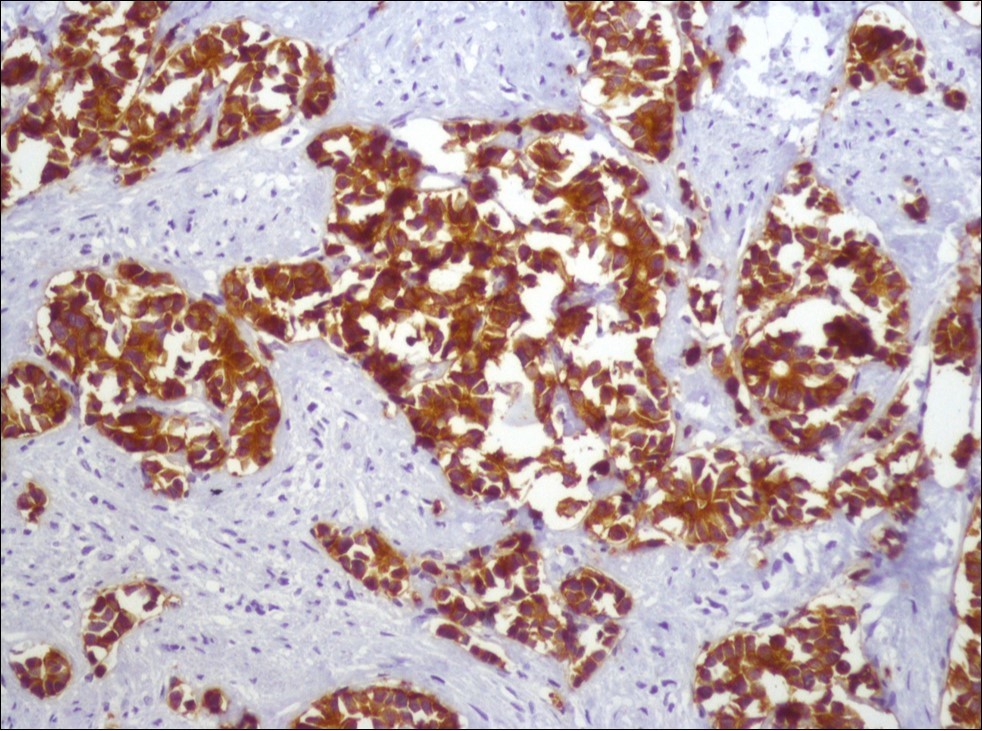

A 73-year-old male patient was admitted to our outpatient clinic with acute urinary retention. Digital rectal examination was normal. The PSA value was 1.81 ng/dl. Prostate size was 101 cc. Since the PSA value and digital rectal examination were normal, no biopsy was taken. Ultrasonography showed bilaterally ureterohydronephrosis. The creatinine level was 2.89 mg/dl. Hypertension has been presented as a comorbidity. An 18 Fr Foley catheter was inserted and alpha-blockers and 5-α reductase inhibitor medication was given. Creatinine level decreased to 0.91 mg/dl after one week. When the patient's catheter was pulled out, he could not urinate again. A catheter was inserted and waited one week more. After one week, the patient was unable to urinate again. The operation was decided due to this recurrent urinary retention. Because of prostate size was 101 cc and prostatic urethra was long, open prostatectomy was decided. When the prostate was removed during the operation, it was evaluated that the left side and the lower side were adhered to surrounding tissue. The prostate was removed as an en bloc. The catheter was removed after 5 days. The pathology of the patient has been reported as pure small cell prostate carcinoma. On the microscopic examination, the tumor was heavily infiltrated into the prostate parenchyma (Figure 1). Tumor cells were consist of atypical small-medium sized, mitotically active cells with a high nuclear to cytoplasmic ratio, hyperchromatic nucleus, nuclear molding, and inconspicuous nucleoli (Figure 2). On the immunohistochemically examination of synaptophysin showed diffusely and strong positivity while chromogranin A showed focal weak positivity with the absence of staining for PSA (Figure 3). Ki67 proliferative index was equal to 90% of the tumor cells (Figure 4). The results confirmed the diagnosis of prostatic small cell carcinoma. Metastatic lymph nodes were detected in the right perirectal region with metastatic multiple lymph nodes in the bilateral external iliac region, more on the left than in the PET CT. No metastasis was detected in the brain MRI and thorax computed tomography. Four cycles of etoposide and cisplatin chemotherapy were administered to the patient. Control PET CT taken after chemotherapy showed a significant decrease in size and metabolic activity of the right obturator and lymph nodes in the right perirectal area. The size and metabolic character of the left obturator, left external iliac and common iliac lymph nodes were increased. After a month, patient admitted to emergency outpatient clinic with left flank pain. There was an 8-cm mass in retroperitoneal area in the computed tomography. Supportive treatment was started because the patient could not tolerate chemotherapy. The masses reached to 13x11cm and fulfilled the retroperitoneal area. Multiple lung metastases were seen. The patient died 13 months later after the first diagnosis.

Figure 3.Diffusely and strong immunostaining for synaptophysin (Synaptophysin, x200)